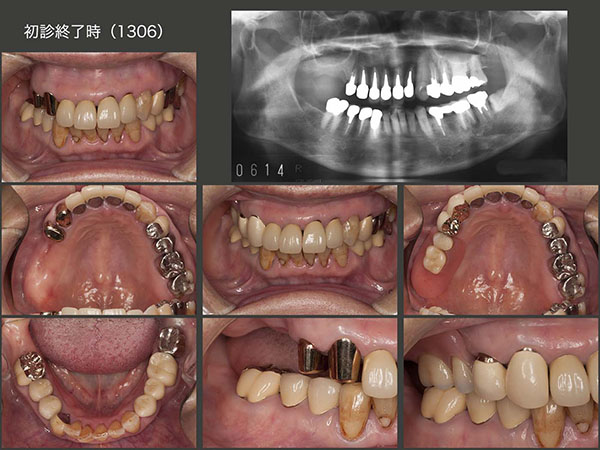

今回は右側の治療を行いたいとの希望で,まず右下3にメタルボンド冠,右下6に硬質レジン前装冠を装着した.一番問題となる右上の補綴設計は,支台歯となる右上3,4に太くて長いメタルコアが入っているため,何時歯根破折が生じてもおかしくない状態であった.そこで,将来の変化に対応しやすいコーヌス義歯を選択した.しかし,主な咀嚼側は歯が咬み合っている数の多い左側になるので,そこまで右側義歯の予後を心配しなくても良いと高を括っていた.2013年6月に取り敢えず治療を終了した.

治療終了7ヵ月後の2014年1月,恐れていた歯根破折が左上5に生じた.このことは,右上に義歯を装着するときに,耳にたこができるぐらい説明してきたので,すんなり左上の治療を受け入れてくれた.11月に,上顎左側にも可撤式ブリッジ(コーヌス義歯)を装着した.

2015年5月,これも恐れていたと言うより予想どおりであるが,右上に問題が生じた.強いて言えば,もう少し年を重ねた先に起こるのでは?また,右上4が先に歯根破折すると思っていた.ところが実際は右上3に歯根破折が生じた.幸い破折線が根尖まで達していなかったので再植することができた.しかし,右上3は支台歯として力,特に水平力を担うには,歯根が短く無理があるため,残りの前歯4本を支台歯として組み込み,上顎の支台歯全てを2次固定し,全体で力に対抗できるようにした.

2016年7月,上顎一体型のコーヌス義歯が完成した.固定効果は十分に得られるが,右上4および左上4は無髄歯であることから,将来の歯根破折が心配であることに変わりはない.一方,左下6の根尖病巣はまだそのままであり,左下7の遠心の歯周ポケットも深い.本来は左下の治療も必要であるが,痛みがまだないので本人の治療承諾が得られていない.